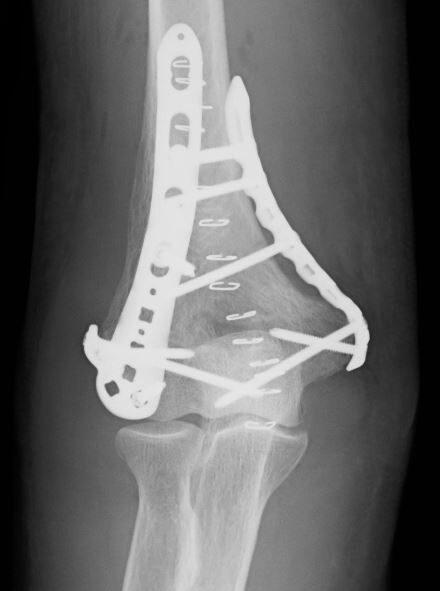

昔からさまざまな術式が報告されていますが、決定打が無い状況です。dual plate (locking plate)、double TBW、クロスでの cannulated screwなどたくさんの報告があります。

ただ、全身状態が良好で ADLもそれなりにあるの場合は、術後の後療法の容易さから dual plate (locking plate)が選択されます。今回は DepuySynthesの VA-LCPを使用しました。

やはり、尺骨神経の処理がポイントになると思います。今回は、まず肘部管を開放してから、骨折部の整復およびプレート設置を行いました。尺骨神経は皮下に移行しています。

何とかワン・ターニケットで手術を終了しましたが、いつやってもしんどい手術です。まぁ、その夜のビールは美味しかったですが(笑)。